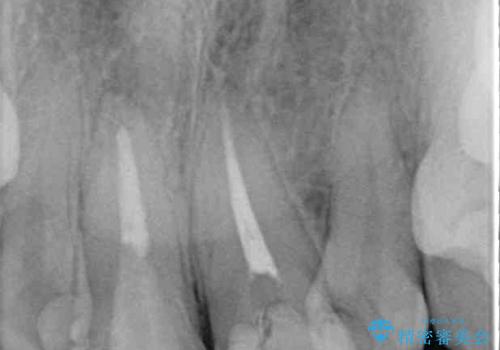

レントゲン写真より、歯根の炎症が認められず、土台もしっかりと植立されていたため、仮歯に置き換えた後にオールセラミッククラウンにて補綴することとしました。